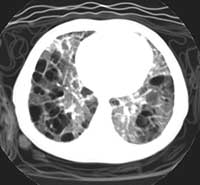

This xray prompted a referral to the Chest Service, with an urgent CT of this child's chest.

ENLARGE

this CT scan.

DOES THIS CHANGE YOUR INITIAL DIFFERENTIAL DIAGNOSIS?